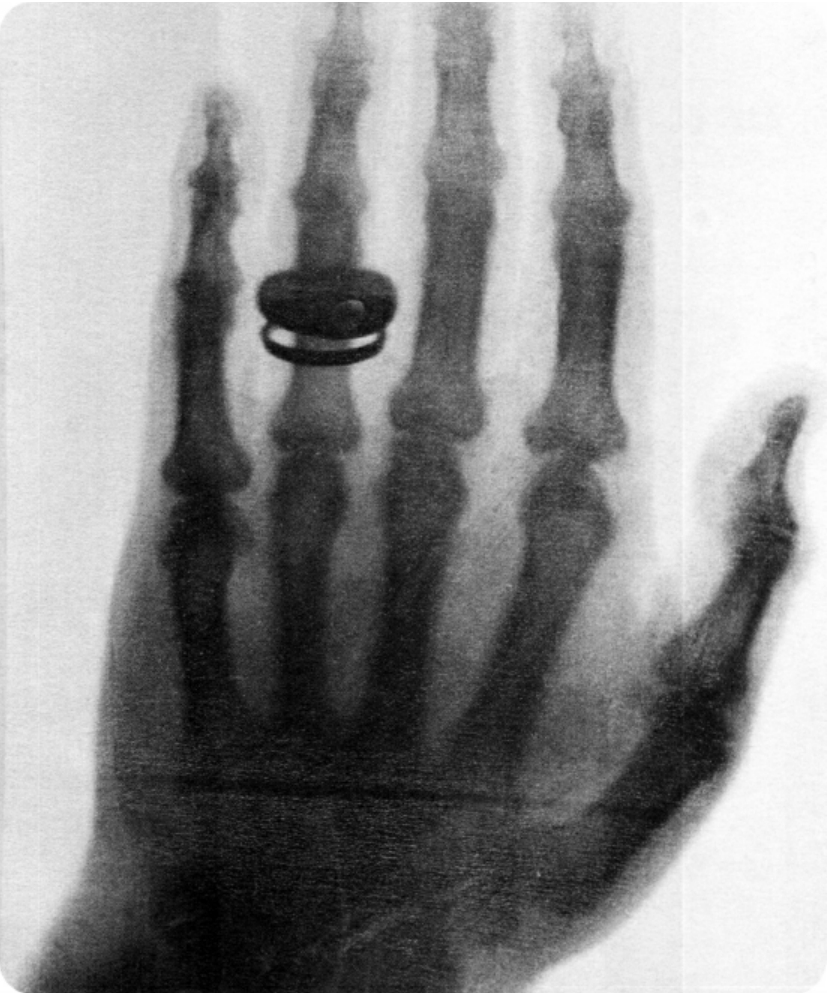

伦琴拍下的他夫人手骨的照片

说起来也许令人觉得奇怪,任何一个法国物理学家都没有像彭加勒那样为X射线的发现所高度激动。1896年1月20日在法国科学院周会上,彭加勒把伦琴托人带给法国科学院的X射线照片(那是一张伦琴夫人手骨的照片)给大家看。